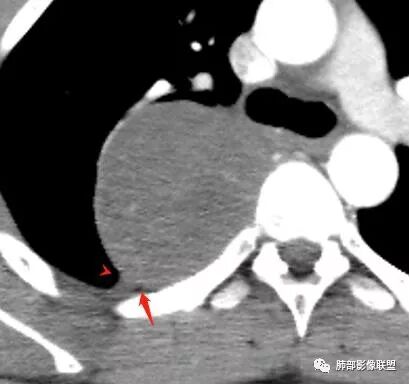

这是哪根血管供血?

长沟流月去无声:

这根看强化

是体循环供血

脏层胸膜主要由支气管动脉和肺动脉供血,壁层胸膜主要由支气管动脉,胸廓内动脉、肋间动脉供血

如果是肋间动脉,就不可能是脏层胸膜,可以是壁层或者纵膈

但是这个病人,肋间动脉供血吧,我倾向胸膜

看血供来源(体循环),脏层来源需要打个问号了

这个血供显示的较清楚

逐步强化

肋间动脉供血,强化尚均匀,逐步强化

供血,体外供血,体循环,要么是壁层胸膜,要么胸膜外的,脏层胸膜应该是对内供血。病变里面的血管,除非是非常粗大迂曲的血管,不然,我不认为是其特点。

脏层胸膜肺内供血,壁层胸膜体外供血

这个病人不是肺动脉与支气管动脉供血,是肋间动脉供血